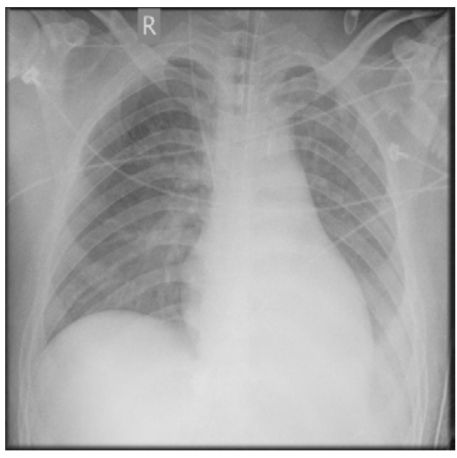

5. 病人男性59歲於午夜24時,突因胸悶並有牙床緊疼,乃直往急診部求診,時病人之T/P/R = 35.1/51/18, BP 137/74 mmHg; 理學檢查,未見任何異常。病史追尋,本病人曾經醫師確定高血壓、高脂血、糖尿病及攝護腺肥大,唯僅只服用Bisoprolol 2.5 mg/day。經緊急檢查:其心電圖及胸部X光顯示如圖:生化檢查: CK,96 U/L;CK-MB,20 U/L;TnI <0.0012 ng/ml;Sugar 252 mg/dL; Na,137 mmol/L; K, 3.7 mmol/L; TG,182 mg/dL and Total cholesterol, 222 mg/dL ; 血液檢查: Hb,13.9 g/dl; Platelet, 203 K/uL; WBC,9.45 K/uL; Cre,1.3 mg/dL 請問本病人最可能的急診診斷是:

(A) Printzmetal's angina (B) Aortic dissection (C) Acute anterior myocardial infarction (D) Hypertension (E) Acute periodontitis disease